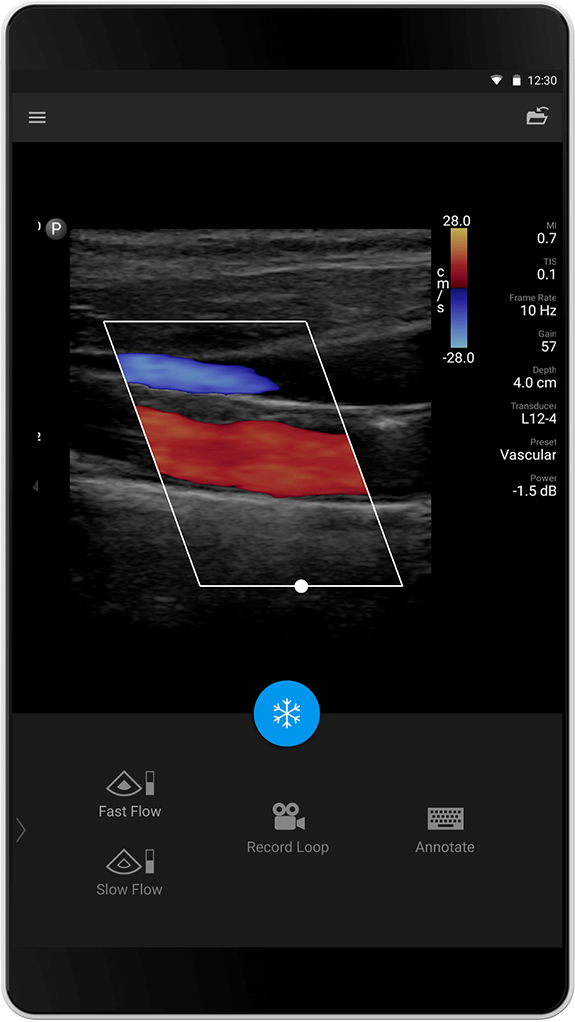

Forhåndsinnstillingen (preset) for Soft Tissue (Bløtvev) er utviklet for avbildning av organer som bryst, skjoldbruskkjertel og testikler. Denne optimaliseringen fremhever kontrastoppløsning og detaljer for visualisering av bløtvevsstruktur. Sensitiv optimalisering av color flow muliggjør detaljert deteksjon av color flow for programmer som feks. utelukker testikkeltorsjon.